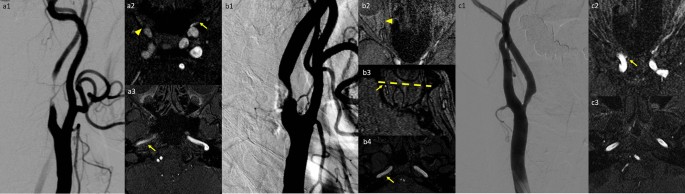

Demonstration of the three imaging parameters in three different patients with different stenosis percentages of the internal carotid arteries (ICAs). (A) Nearly total occlusion of the right ICA. Right grade 3 (arrowhead in A2 for no visible opacification of the ophthalmic artery) and left grade 2 (arrow in A2 for distal end of the ophthalmic artery opacification) of the ophthalmic artery opacification were depicted. Decreased diameter and signal intensities of the right petrous ICA (arrow in A3) compared to the contralateral side were noted. (B) Right ICA with 77.2% stenosis. Right grade 2 (arrowhead in B2 for distal end of the ophthalmic artery opacification) and left grade 1 (arrow in B3 for distal end of the ophthalmic artery opacification; the dotted line indicated the level of the posterior border of the globe) ophthalmic opacification were noted. Slightly decreased signal intensity without significant diameter discrepancy of the right petrous ICA (arrow in B4) compared to the contralateral side were demonstrated. (C) Left ICA with 59.4% stenosis. Bilateral grade 2 ophthalmic opacification with a tiny ophthalmic artery budding from the right ICA (arrow in C2). No significant discrepancy of signal intensities or diameter are depicted between bilateral petrous ICAs (C3).